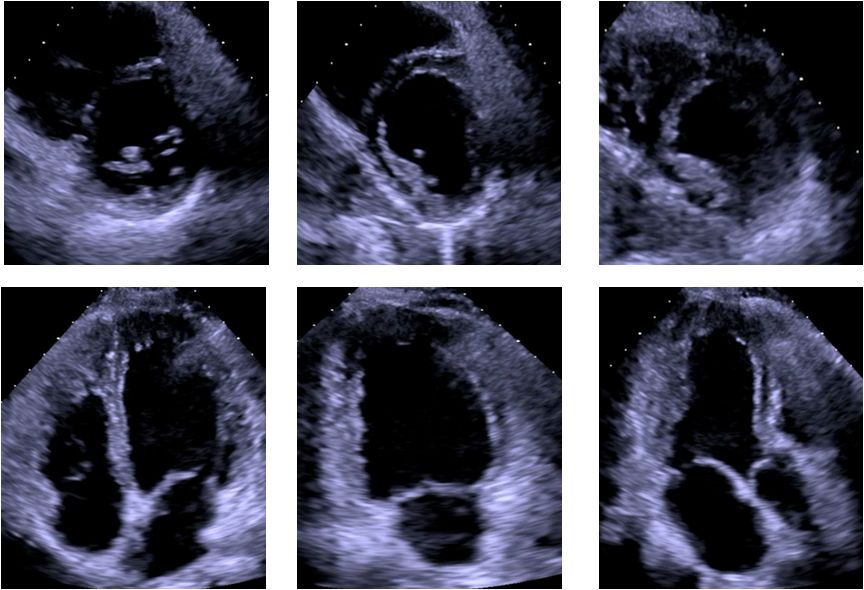

▶▷ 2018年10月29日-31岁男性,心力衰竭入院